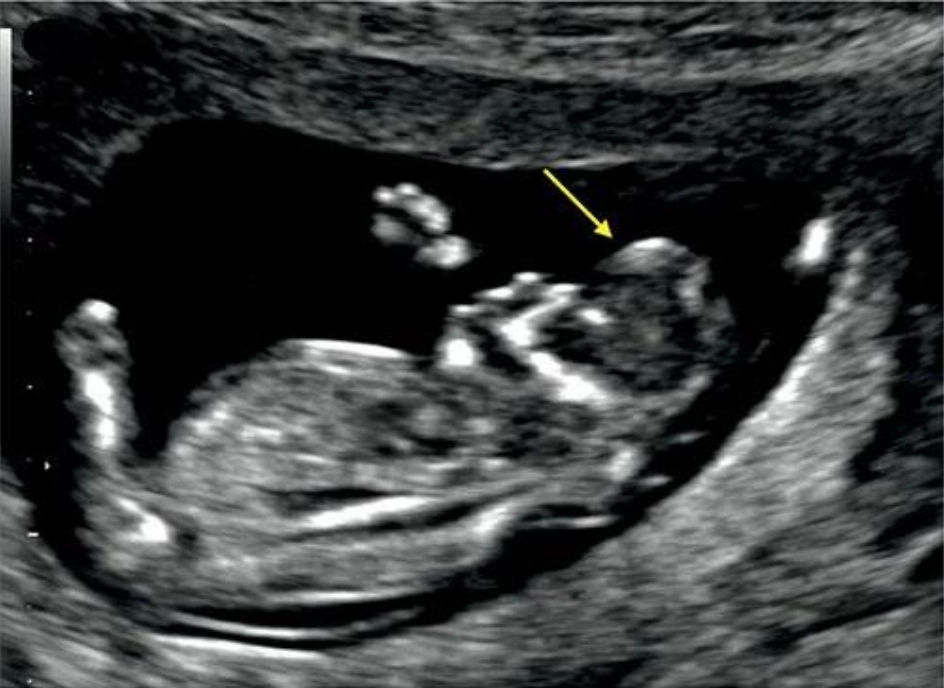

Tật chẻ đôi đốt sống thể hở (Open spina bifida)

16/03/2026